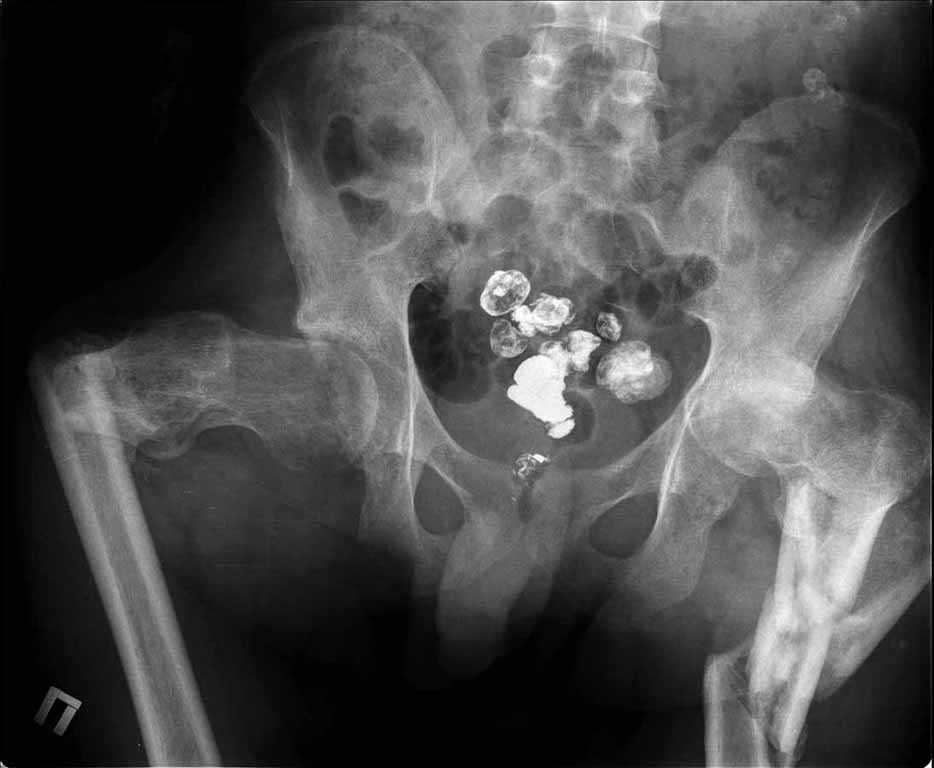

Пациенту 22 года. Травма в июле 2010г, лечился в районной больнице. К нам попал в апреле 2011г.Тяжелая сочетанная травма (29.07.2010): тупая травма живота с повреждением внутренних органов. Закрытая травма грудной клетки с переломом ребер. Пневмоторакс справа. Тяжёлая позвоночно-спинномозговая травма. Закрытый осложнённый переломо-вывих С5 позвонка. Верхний парапарез, нижняя параплегия, нарушение функции тазовых органов по типу недержания. Цекостома. Пролежень левой ягодичной области. Неправильно консолидированные переломы верхних третей обеих бедер. Застарелый вывих левого бедра.Осложнение: Поддиафрагамльный абсесс слева, забрюшинного пространства. Свищ желудка и ободочной кишки. Синегнойный сепсис. Двухстороняя пневмония. Но это уже анамнез.Пациент был неоднократно оперирован на органах брюшной полости и осложнениями с ними связанными.

В ягодичной области слева глубокий пролежень размером 2х2см, дном является вывихнутая головка бедра. Неврологически в нижних конечностях динамика положительная, появились движения в правой стопе, чувствительность в стопах.По переломам бедер: подвижности в местах переломов нет, снимки высылаю.

Мне кажется, что нудно начать с резекции головки левого бедра (как минимум - вы устраните очаг хр. инфекции) далее заниматься закрытием стом и правой стороной (судя по неврологической динамике).К левой стороне можно вернуться позже, если понадобится.